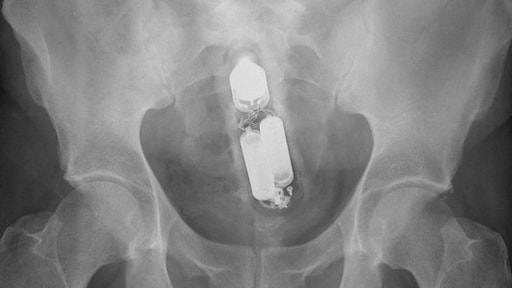

"Bierflesjes, wortels, tandenborstels, vazen en stenen, als het past, gaat het erin", zegt ze. Daar kunnen normen of richtlijnen weinig aan voorkomen. Wat wel zou helpen, is minder schaamte. De röntgenfoto's zijn afkomstig van een website voor en door artsen, waar zij foto's delen als naslagwerk.